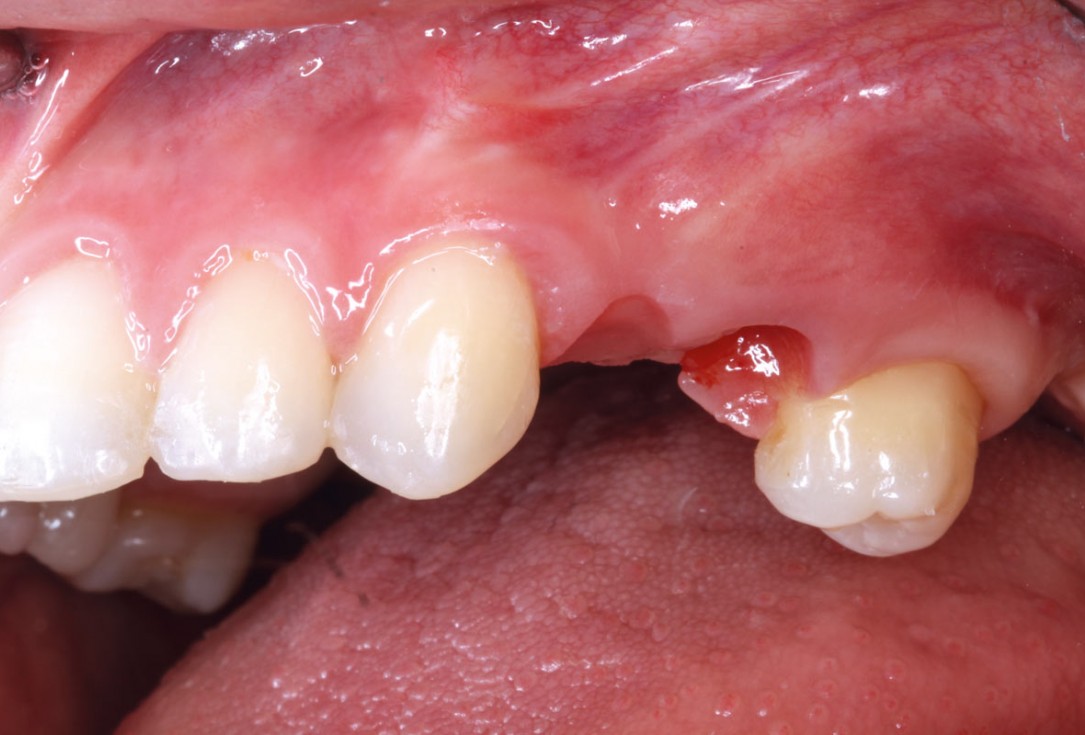

5/11 - Clinical situation after six months healingRidge reconstruction with maxgraft® block in the posterior maxilla - Dr. A. Puišys